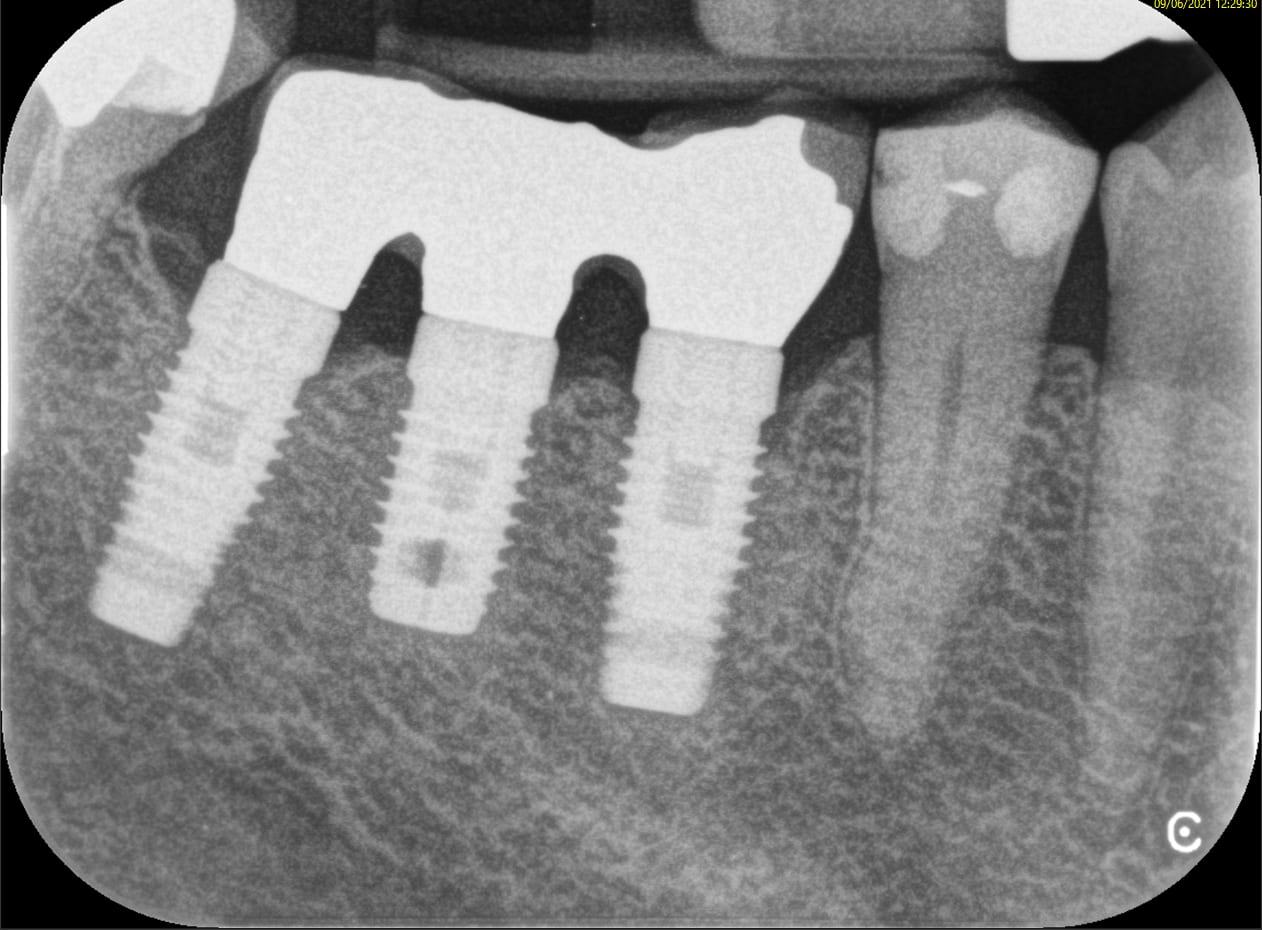

Bonjour à tous

Petite question identification...

Secteur 14 /15

Avez vous une idee ?

je pense a des anthogyr ou eurotechnika...

pas sur...

Merci

9a7lkd6rxj66pn408lzxo83mvfu3 - Eugenol

Rétro stp

Pas assez de détails sur une pano